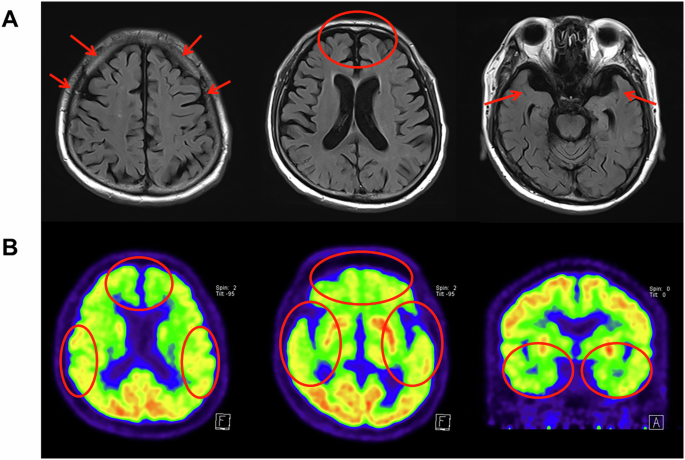

A 75-year-old right-handed man with 10 years of education visited our hospital with cognitive impairment. He complained of progressive memory difficulties for 4 years from the age of 71 years. The patient’s initial symptom was his inability to recognize his grandchildren, sometimes without problems in daily life. He scored 27 on the Mini-Mental State Examination (MMSE), and routine laboratory test results were normal. The patient was diagnosed with the mild cognitive impairment without further evaluation. Two years later, his memory had noticeably declined. His MMSE score was decreased to 24. The first brain magnetic resonance imaging (MRI) scan showed the atrophy in the temporal lobe, and mild hippocampal atrophy was observed. 18F-fluoro-deoxyglucose positron emission tomography (18F-PET) revealed bilateral temporal lobe hypometabolism. Neuropsychological testing revealed memory, language, and executive dysfunctions. The patient was diagnosed with early AD dementia, and acetylcholinesterase inhibitor donepezil was initiated. Five years later, he presented with a deterioration of cognitive deficits. He had difficulty recognizing acquaintances and was fired from his security job. He wandered home and was unable to find familiar routes. He did not take care of personal hygiene and developed apathy and abulic symptoms. He scored 16 on MMSE, indicating a marked decline. A follow-up brain MRI revealed the progression diffuse brain atrophy (Fig. 5A, Supplementary Fig. 1). 18F-PET also revealed the aggravated hypometabolism in both frontotemporal lobes (Fig. 5B). The patient’s family history could not be fully defined; however, the possibility of familial disease could not be ruled out. Both parents of the patient died during the Korean War in the 1950s. Information on grandparents or patient’s siblings were not available. The patient had five siblings; three older siblings died of old age, and two younger siblings were in their 70 s. None of the siblings had any neurodegenerative symptoms, and all family members refused genetic testing.

A Diffusion brain atrophy on brain MRI scan. B Hypometabolism of both frontotemporal lobes on 18F-fluoro-deoxyglucose positron emission tomography scan. The red marks indicated the relevant areas.